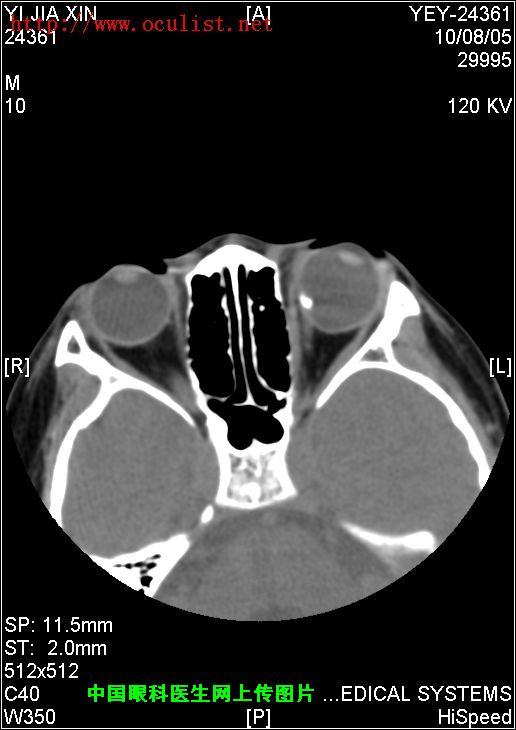

患者男,9岁,发现左眼外斜9年,检查:左眼视力0.01(矫正不应),左眼外斜400,角膜、晶状体未见异常,眼底如下图,CT如下图,RMI暂无,请分析一下该患儿的诊断?

眼底图和CT片: